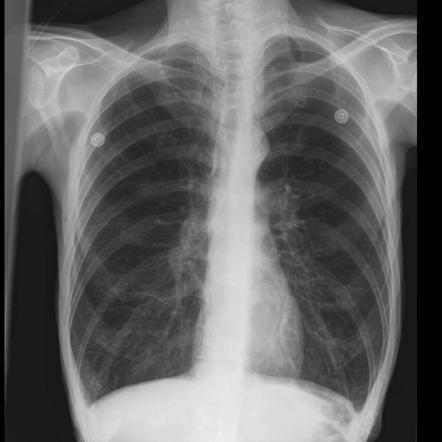

Describe the abnormality/ies

Sail sign (left lower lobe collapse)